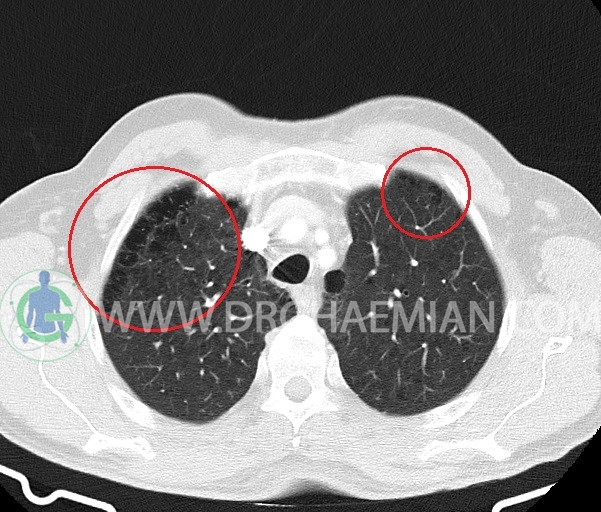

– آمفیزم سنتری لوبولار در لوب فوقانی هر دو سمت با ارجحیت در سمت راست

–آمفیزم پاراسپتال در هر دو ریه

–ندول Solid با حدود صاف به سایز 6x5mm (متوسط 6mm) در سگمان پوستریور بازال لوب تحتانی راست (تطبیق با مدارک قبلی )